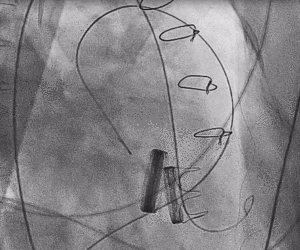

1.术中经股静脉入路,送入指引导管、导丝,成功跨瓣,建立导丝轨道。

2.进行预扩张。球囊打开时未见明显腰征,预扩张球囊顺利打开梗阻瓣膜。

3.经股静脉入路送入16F E-sheath可扩张导管鞘,随后送入SAPIEN 3球扩瓣1输送系统,由于肺动脉入路朝上走,无需调弯,顺利跨瓣,将SAPIEN 3球扩瓣送入预定位置。精准定位后,以160次/分快速起搏,并保证1:1完全夺获,缓慢释放瓣膜。术后超声检查结果显示即刻跨瓣压差从术前9mmHg降至3mmHg,顺利完成瓣膜释放,回撤导管、导丝。